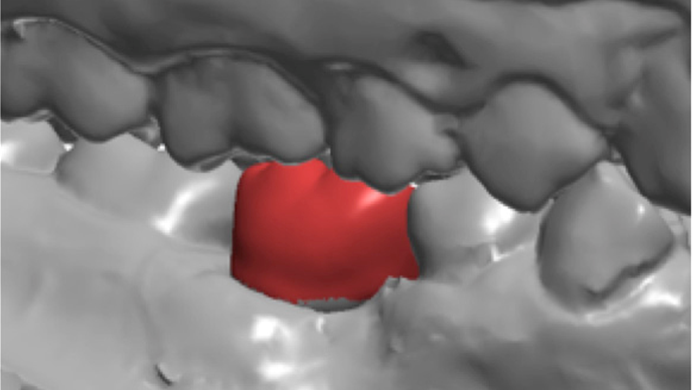

Clinical case: # 46 implant placement & GBR using i-Gen membrane for significant vertical resorption & mixed bone defect

- Courtesy of Dr. Iulian Filipov, Romania -

AnyRidge, mandibular posterior, i-Gen, resorption, bone defect, bone regeneration, space management, #46, GBR, Dr. Iulian Filipov

AnyRidge implant system, i-Gen